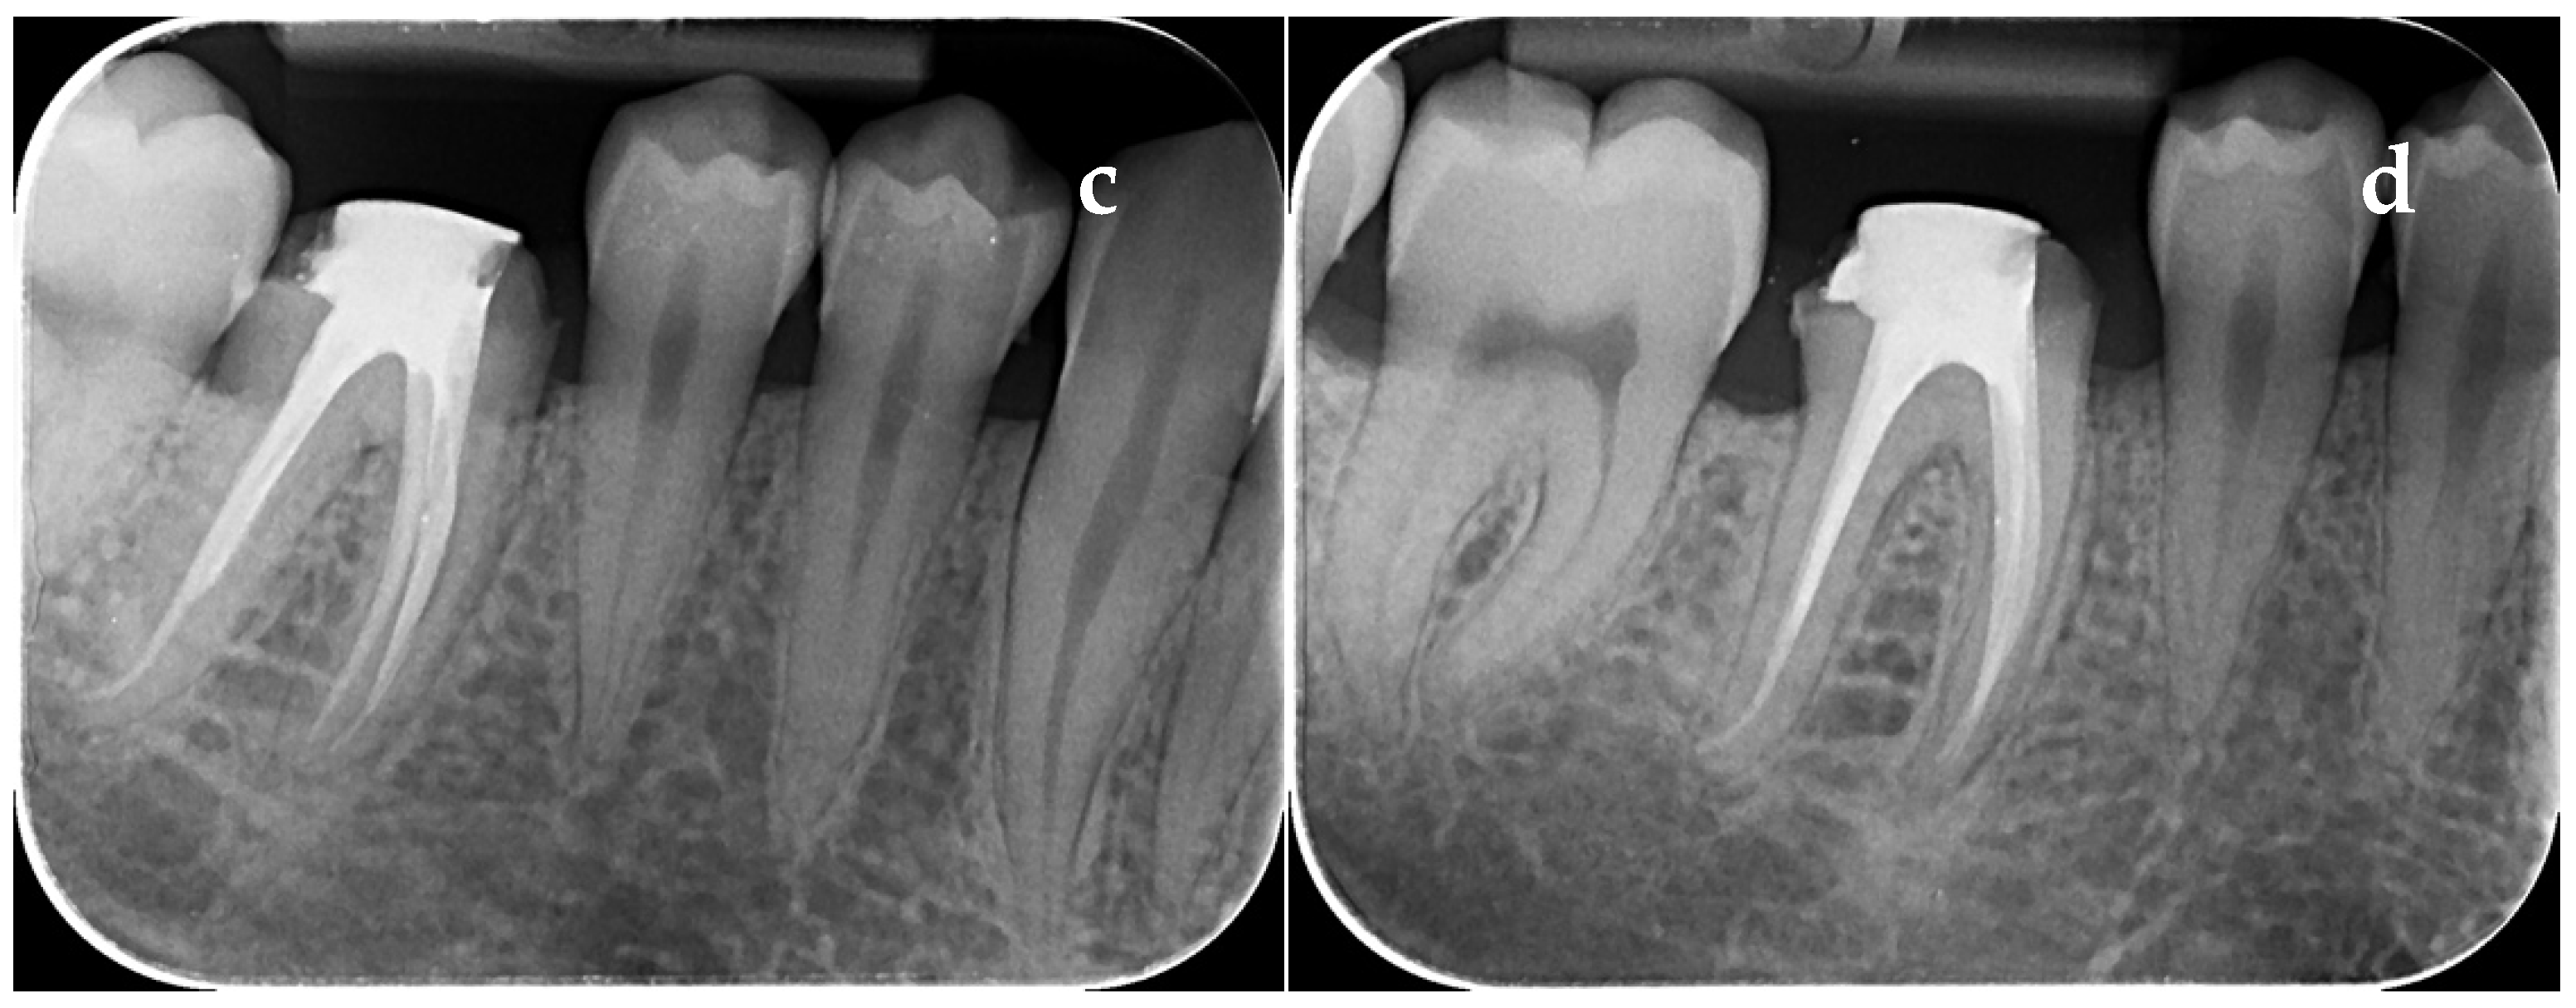

3.2. Paraclinical Evaluation

3.2.1. Evaluation of the PAI Score on Group with Dehydrated Plant Extract

3.2.2. Evaluation of the PAI Score on Group with Calcium Hydroxide